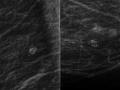

Bases físicas da mamografia